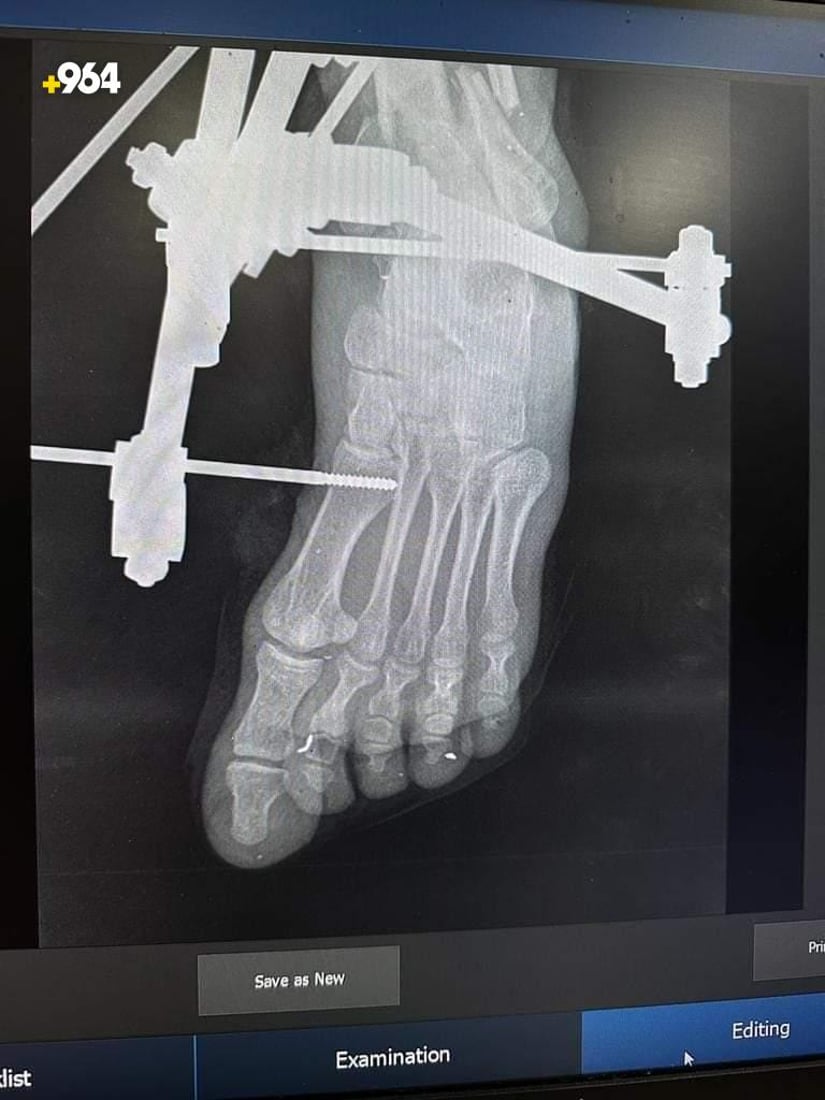

صور: أطباء ينجحون في تثبيت كسر مضاعف أسفل الساق لمصاب في تلعفر

نجح فريق طبي في مستشفى بلدة تلعفر العام بنينوى، اليوم الاثنين، من تثبيت كسر أسفل عظم الساق لشاب، بعد عملية جراحية نادرة، وفقاً لإدارة المستشفى.

المريض كان في حالة صدمة وعائية عقب إصابته بانفجار جسم غريب، ويرقد في ردهة الجراحة بمستشفى تلعفر ويتلقى العلاج، وما زال الفريق المعالج يتابع وضعه الصحي بعد تكلل العملية بنجاح.

الفريق الذي ترأسه الدكتور زكريا ربيع، اكتشف نتيجة الفحوصات أن الشاب يعاني من كسر مضاعف أسفل عظم الساق الأيسر، إلى جانب جرح تهتكي وفقدان في الانسجة الرخوة.

الفريق نجح في تثبيت الكسر بالمثبت الخارجي بعد إجراء الإسعافات الأولية.